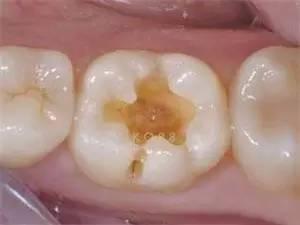

中龋

如果前期龋坏没有进行修补,龋坏就会加深,也就是到了中度龋坏,这个时候对冷热酸甜就会出现疼痛反应,当刺激源去除后疼痛也就会消失,没有自发性疼痛。

这个阶段也是可以用多种补牙的方式进行修复。